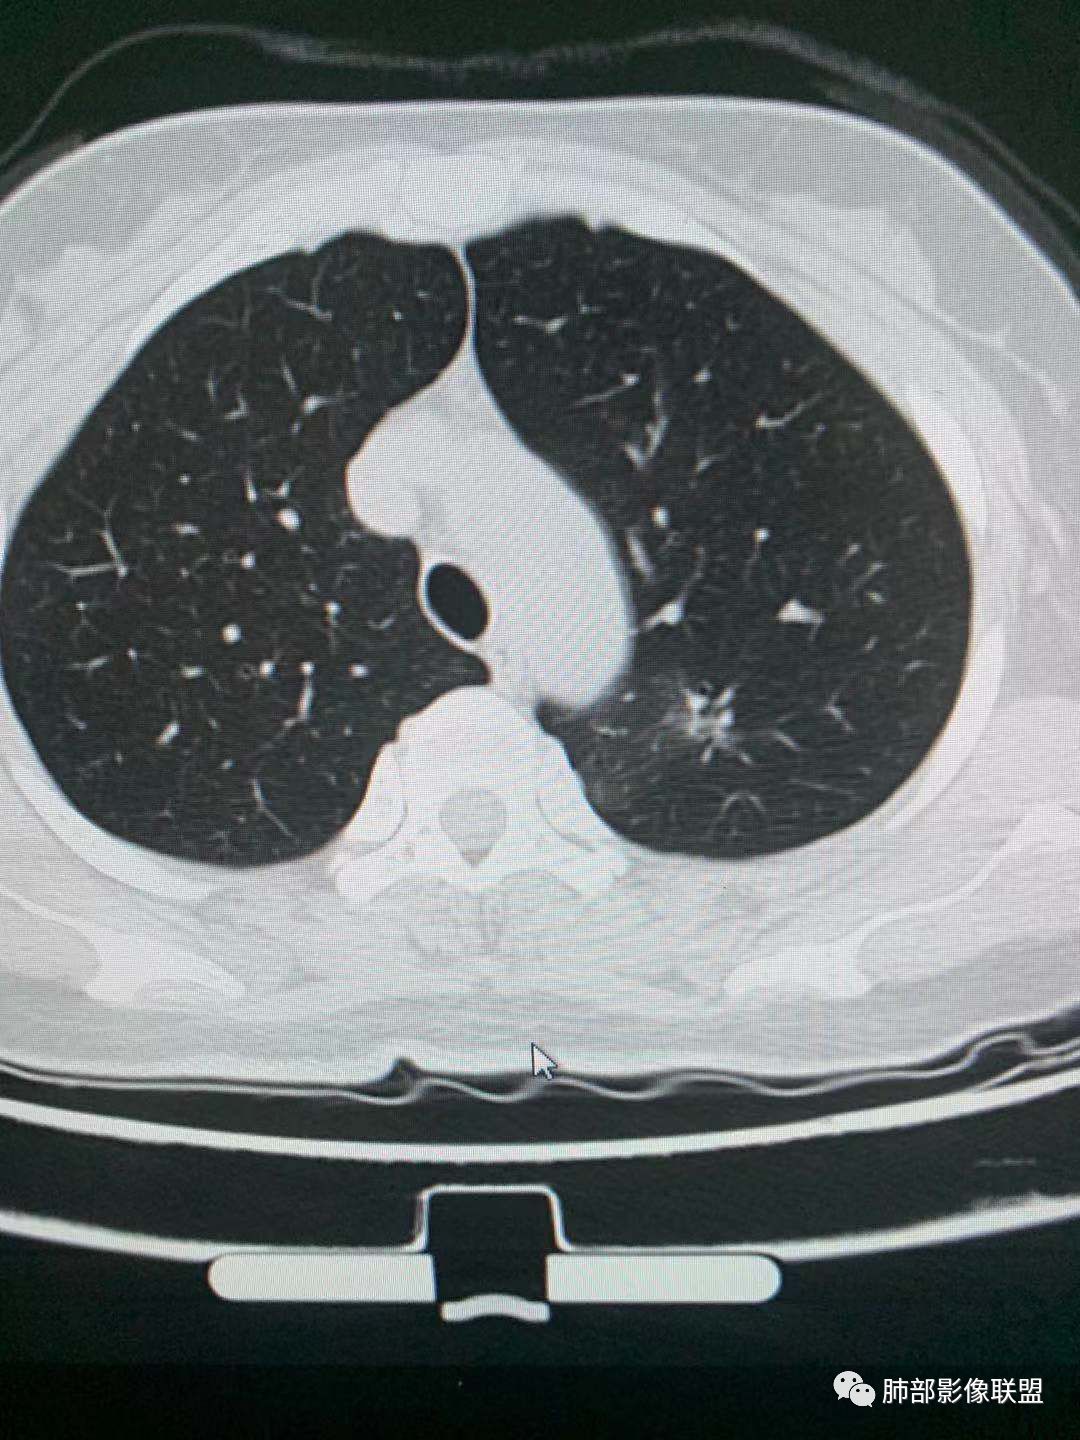

二.左肺上叶前段磨玻璃结节:

该结节较大,边界清楚,小叶间隔阻挡特征相当明显,微浸润腺癌的诊断几乎没有争议!

三.右肺上叶胸膜下结节及左肺上叶血管旁结节,尽管都是磨玻璃密度,但都比较小且边缘特征不明显,恶性征象未显露,处置并无特殊,定期复查!